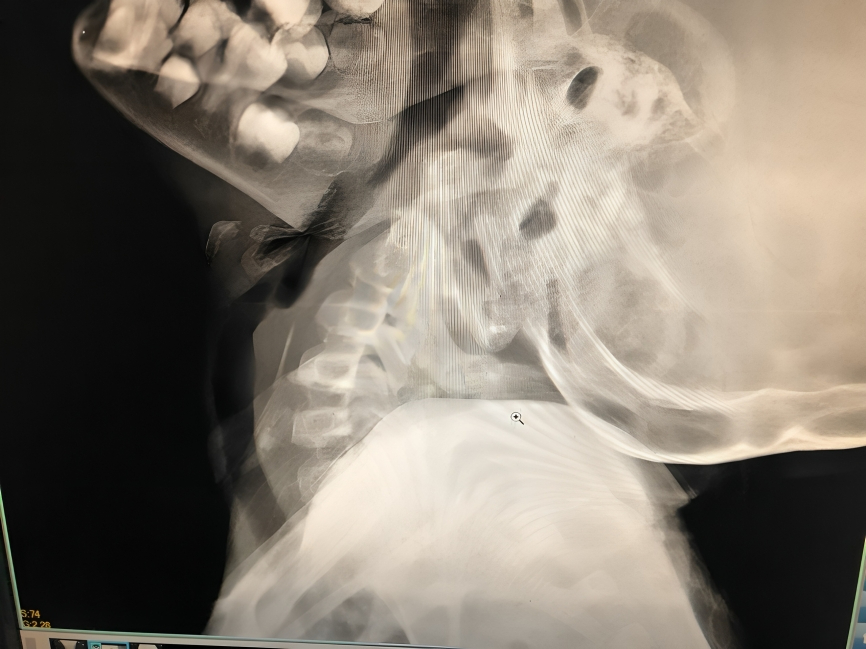

Experience expert, reliable and compassionate ENT care when it matters most. Dr. Ashok Garje delivers advanced diagnosis and specialized treatment for ear infections, nasal obstruction, throat disorders, hearing loss and sinus diseases - ensuring precise care, faster recovery and long-lasting relief for every patient.

Comprehensive care for ear infections and hearing loss, including Tympanoplasty, Mastoidectomy, Ossiculoplasty and Stapedotomy/Stapedectomy for improved hearing outcomes.

Advanced treatment for nasal blockage, sinus disease, allergies and watery eyes with Endoscopic Sinus Surgery, Septoplasty, Rhinoplasty, Dacryocystorhinostomy and Endoscopic DCR.

He is skilled in endoscopic evaluations, minimally invasive ENT procedures, vertigo assessment and advanced ear - nose - throat care, ensuring precise and patient-friendly treatment.